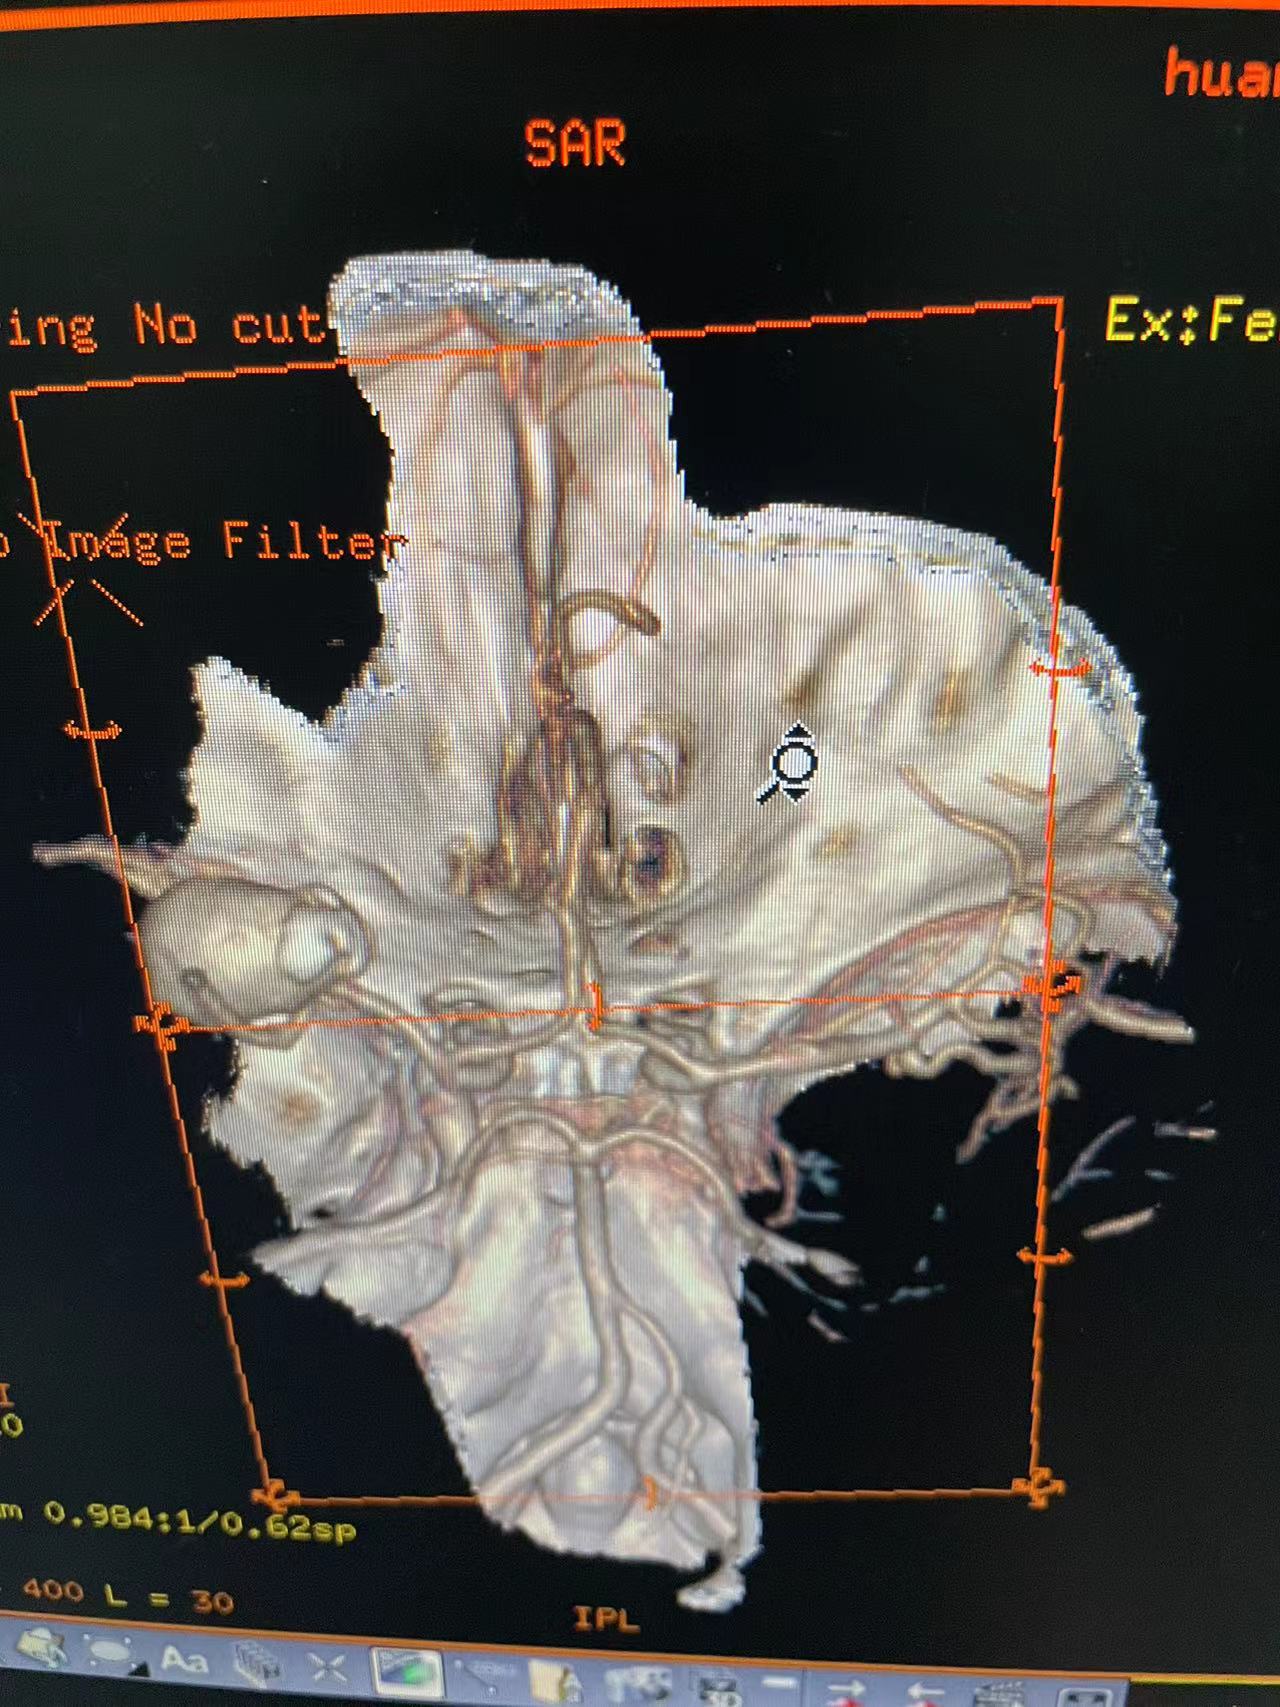

工作笔记:

HRQ、女,66岁,463177,因头昏头疼2天,吐词不清1天于20230203日16时24分入院。右侧肢体肌力四级。

指导手术者:成都中医药大学附属医院神经外科主任李定君教授。

既往患者肾上腺嗜铬细胞瘤术后,患者血压波动大!

夹闭术后两个月,出院后一个月!再次出血,血肿量大,患者清醒!转上级市级医院,拟予介入栓塞后清除血肿

家属选择保守治疗,患者一直清醒!两个月前在华西行介入栓塞术,血肿吸收!

介入栓塞术后两个月来复查!患者清醒轮椅而来,言语稍含糊,右侧下肢肌力可大于三级,上肢一级!